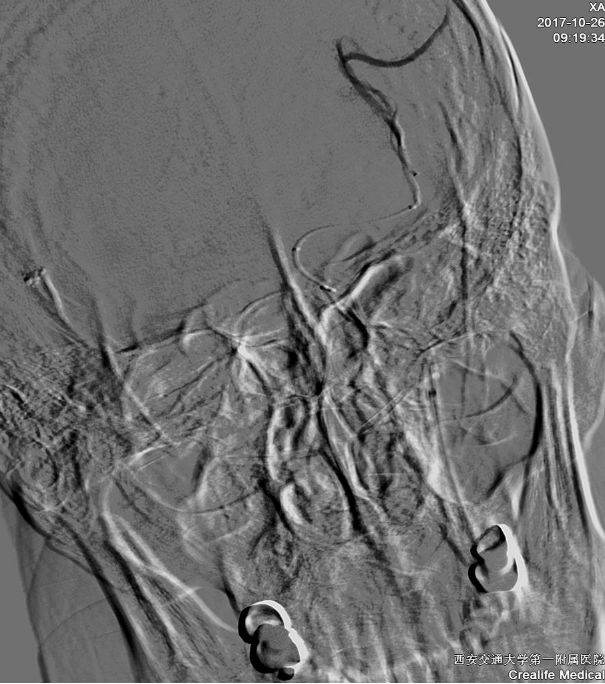

术前CT

ASPECTS评分 8分

术前造影:

串联病变

ASITN/SIR 2级

球囊扩张

微导管在血栓远端造影

支架到位释放透视图+造影图

异常早显静脉

取出栓子

术后正侧位造影图片

术后即刻CT

术后24h CT